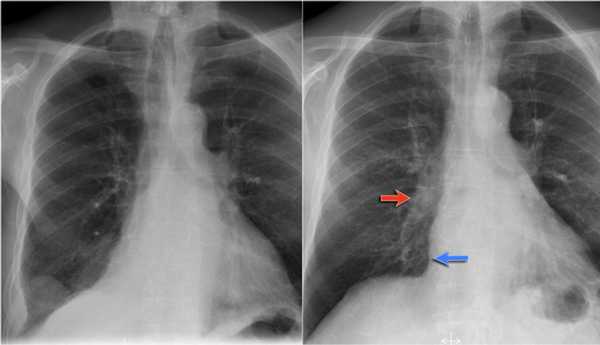

Также очень частым проявлением ателектаза является подъем диафрагмы, что хорошо визуализируется на ниже представленной рентгенограмме (указано синий стрелкой).

У данного пациента карцинома легкого с билатеральным метастазированием в легкие (указано красными стрелкам).

Ателектаз средней доли правого легкого.

- Симптом силуэта — нечеткие границы правых отделов сердца.

- Трехгранные изменения высокой плотности, визуализирующиеся на боковой рентгенограмме, являются результатом ателектаза средней доли правого легкого.

При ателектазе средней доли правого легкого подъем диафрагмы навсегда значительно выражен.

Ателектаз нижней доли правого легкого.

На нижепредставленой рентгенограмме пациента 70 лет, упавшего с лестницы, в плевральной полости определяется скопление жидкости, предположительно являющейся кровью.

Это ателектаз нижней доли правого легкого.

Обратите внимание на правую границу сердца. Правая междолевая артерия не видна потому, как она не окружена воздушной легочной тканью, а закрыта спавшейся нижней долей правого легкого.

Ниже представлены последующие рентгенограммы органов грудной полости того же пациента, на которых ателектаз разрешен.

Обратите внимание на правую междолевую артерию (красная стрелка) и границы правых отделов сердца (синяя стрелка).